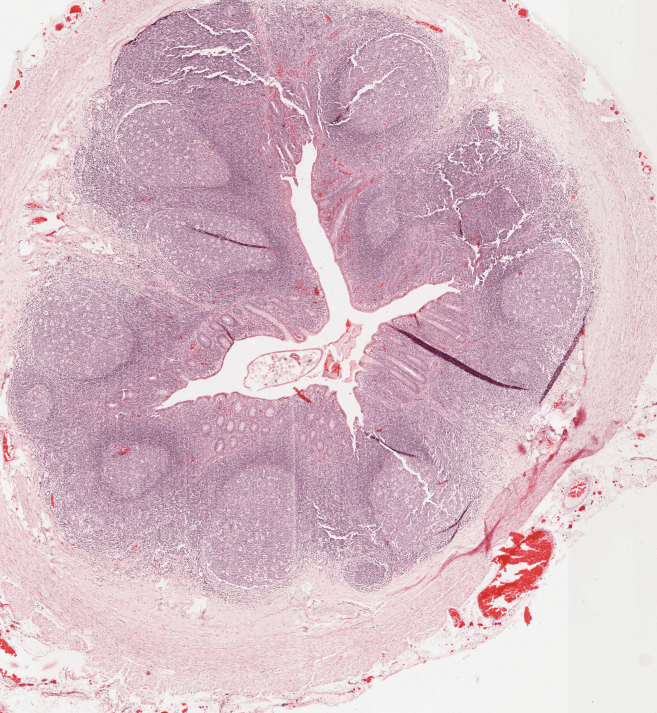

APÉNDICE

El revestimiento del apéndice es similar a la del colon.Esta se caracteriza por exhibir muchos nódulos linfoides en su lámina propia.El apéndice se origina como una evaginación del ciego.En ocasiones es posible observar adipocitos en la submucosa del apéndice.A diferencia del colon, la luz del apéndice es más reducida.La muscular externa del apéndice se conforma de una sola capa de músculo liso de manera longitudinal.Apéndice, HyE.Nódulo linfático secundario ubicado en la Lámina Propia (LP) del apéndice.